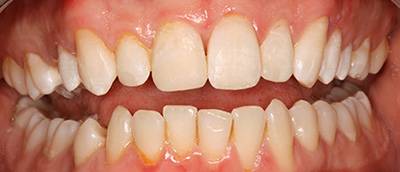

5. eset

Ennek a kedves hölgynek 20 éves álmát váltottuk valóra. 20 évig hordott kivehető fogsorokat. 12 implantátum beültetése után alsó és felső fixen rögzített hidakat készítettünk. Nincs többé kivehető - evéskor, beszéd közben - elmozduló fogsor. Javult a rágási hatékonyság is, amely az egészséges táplálkozás szempontjából is nagyon fontos tényező.